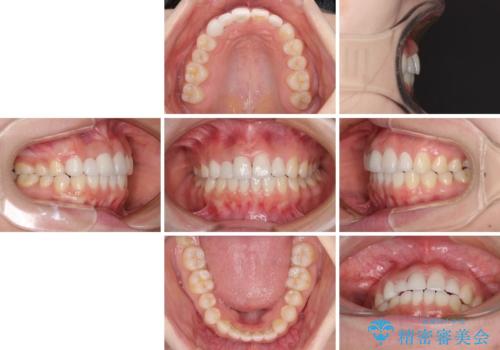

欠損歯と矮小歯 矯正治療と前歯のセラミック治療

欠損による前歯のスペースが大きかったため、事前にワイヤー矯正で前歯の位置を大きく動かし、その後は上下をインビザラインで整えることとしました。

矯正治療後には欠損部はオールセラミックブリッジに、矮小歯はオールセラミッククラウンにて補綴することとしました。

前歯のスペースは、堅い線維の通った歯肉があり、幅も大きかったことから、歯肉切除を行った上でワイヤー矯正により移動を行いました。また、上唇小帯も歯間部付近まで付着していたため、合わせて切除しました。

ワイヤー矯正により、インビザラインよりも早く、歯軸の向きもコントロールしながら移動させることができました。